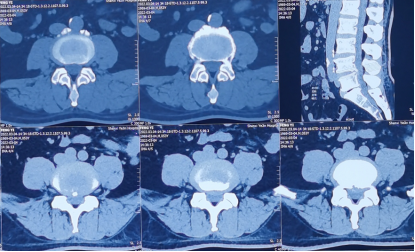

来到陕西冶金医院神经脊柱科后,由张少华主任、熊东主任接诊,经过各项检查后发现他在腰3/4、腰4/5、腰5/骶1都有不同程度的突出,尤其是在腰4/5突出非常严重。鉴于曹先生主要的症状表现和影像学等检查结合,判断腰4/5为主要责任节段,并建议尽快进行微创手术,给神经进行解压。

术前影像学资料